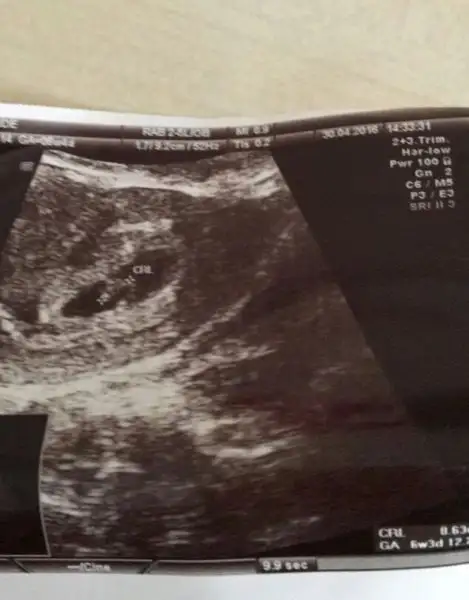

Kiz bence canim :)Merhaba kizlar .. Benimkine de bakar misiniz 8+6 yiz :)Havalianne__

Merhaba kizlar .. Benimkine de bakar misiniz 8+6 yiz :)Havalianne__